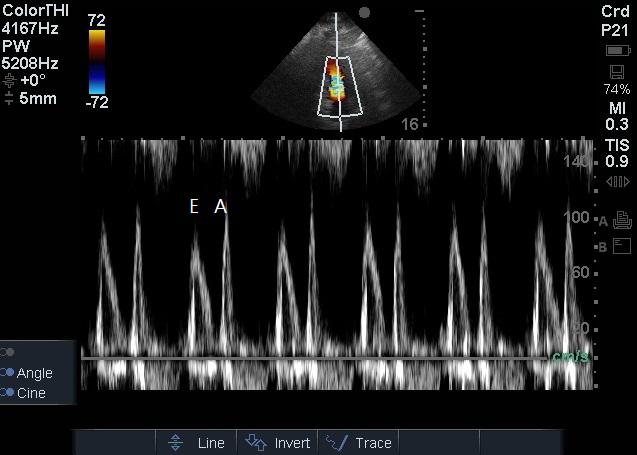

1.2 方法患者入院24 h内完成心脏超声检查。患者左侧卧位,以能显示心尖四腔心切面及五腔心切面为准,以美国Sonosite公司Edge超声诊断系统相控阵探头经心尖对患者二尖瓣、LVOT进行评估,彩色多普勒显示血流束,脉冲型频谱多普勒测量二尖瓣E峰流速及LVOT峰值流速(图 1~2),连续显示多个呼吸周期,选取呼吸周期内血流速变化规律波形,测量血流速最大值及最小值,重复以上过程,每个测量部位血流速共测量三组最大值及最小值,然后计算平均数。二尖瓣E峰流速呼吸变异度=(二尖瓣E峰流速最大值-二尖瓣E峰流速最小值)/[(二尖瓣E峰流速最大值+二尖瓣E峰流速最小值)/2],LVOT峰值流速呼吸变异度=(LVOT峰值流速最大值-LVOT峰值流速最小值)/[(LVOT峰值流速最大值+LVOT峰值流速最小值)/2][1]。

| 图 2 二尖瓣频谱多普勒检查 Figure 2 Mitral valve spectral Doppler examination |

作为心内尤其是左心血流,二尖瓣血流自二尖瓣开放开始持续整个舒张期,在超声频谱多普勒图显示为双峰,第一峰(E峰)为舒张早期心室主动舒张血流充盈左心室所致,第二峰(A峰)为舒张末期心房收缩形成的加速血流,此时心室被动充盈,在舒张期末左心室达到最大容积,随后左心室收缩,血流经左室流出道射入主动脉。作为左心入口及出口的血流,脓毒症患者二尖瓣E峰流速与LVOT峰值流速均数比较差异无统计学意义,提示在LVOT峰值流速难以测量时,参考二尖瓣E峰流速可能有意义;二尖瓣E峰流速呼吸变异度大于LVOT峰值流速呼吸变异度,差异有统计学意义(P < 0.01),提示不能简单地以二尖瓣E峰流速呼吸变异度代替LVOT峰值流速呼吸变异度。